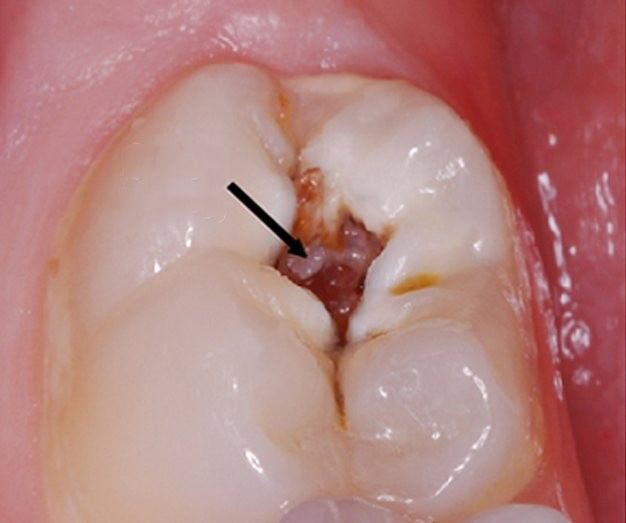

Dişlerimizi gün içinde 2 kere fırçalamak dışında ağız sağlığımıza çok da dikkat ettiğimiz söylenemez. Hele bir de her 6 ayda uğramamız gereken dişçimizi ihmal edince kaçınılmaz sonuçlarla baş başa kalıyoruz. Dişlerimiz düzenli ve iyi temizlenmediğinde çürümeye başlar. Yediklerimizin kalıntıları ağzımızda yaşayan ve çürüklere sebep olan bakteriler için oldukça elverişli bir yaşam ortamı oluşturur. Özellikle yaşlandıkça bağışıklık sistemimiz zayıflar ve durum daha kötüye gider.